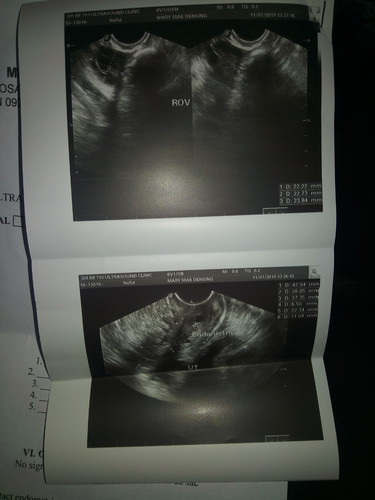

PLEASE READ THIS. hello :) completely gone na ang PCOS ko. 2013 ko nafind out na may PCOS ako after I gave birth to my first son. Though may PCOS ako, regular lang ang mens ko but not until 2017. Di ako hyang sa mga pills o sa metformin. Kaya di ako nagtitake nun. November 2017 di na ako nag mens. Lumobo ang tyan ko na parang buntis ako. Di ako dinugo kaya medyo marami ako health issues. Kaya August 2018, I decided to exercise 30 mins everyday. Sa loob lang ng bedroom ko, close doors and windows, no e-fan. Nonstop dancing for the whole 30mins. Then, I bought virgin coconut oil sa market. Wag yung nasa malls na tig 300... yung sa palengke na pure coconut oil.. sa amin is 100 lang yan. Umiinom ako 2 table spoons before meals. In one month, nag mens ako ng napaka heavy. Nag lose ako ng weight from 100 kilos to 87kilos. Had my TVS and cleared na ang both ovaries ko. Up until now wala na kay buntis na ako ngayon. 2013 when I was diagnosed with it. Took a number of Diane pills and metformin. All of them didn't work. Try nyo lang. Wala naman mamawala kunh itry lang ninyo kasi natural lahat and less expensive than buying meds.

Magbasa paMeron din po ako... Diet lang po. I didn't take any pills or meds. Totally stop Carbs kahit white bread, anything na may sugar lalo na softdrinks, and processed foods lalo na noodles and even hotdogs. Puros gulay and fish lang. I also went to the gym. Di po kasi nagwowork sakin yung pills kasi nahihilo ako though yun yung recommended ng oby ko. Left and Right ovaries ko may cyst at the start. Then after few months yung right natunaw talaga. Yung left meron pa pero maliliit nalang. Nalaman ko may PCOS ako Oct 31 2018. Nalaman kong buntis ako Oct 14, 2019. 🙏

Magbasa paMeron din po ako... Diet lang po. I didn't take any pills or meds. Totally stop Carbs kahit white bread, anything na may sugar lalo na softdrinks, and processed foods lalo na noodles and even hotdogs. Puros gulay and fish lang. I also went to the gym. Di po kasi nagwowork sakin yung pills kasi nahihilo ako though yun yung recommended ng oby ko. Left and Right ovaries ko may cyst at the start. Then after few months yung right natunaw talaga. Yung left meron pa pero maliliit nalang.